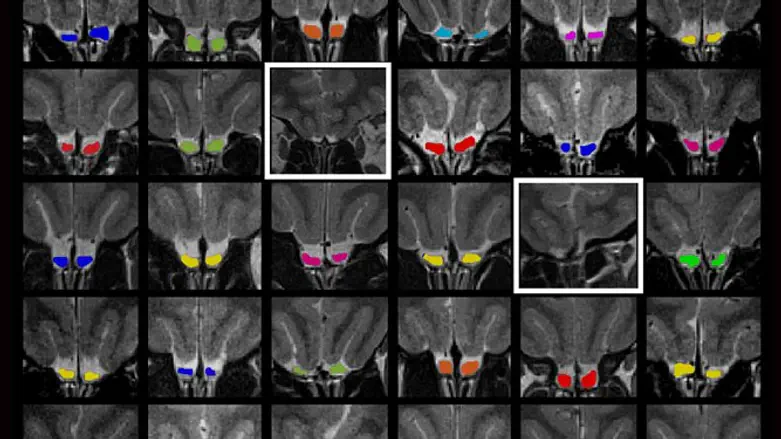

הממצאים החדשים התגלו במקרה, במהלך ניסוי במעבדתו של פרופ' נעם סובל במחלקה לנוירוביולוגיה. ד"ר טלי וייס וד"ר שגית שושן גילו במהלך סריקות מוח בתהודה מגנטית (MRI) במכון הלאומי על-שם עזריאלי לדימות ומחקר המוח האנושי, כי לאחת הנבדקות שהצהירה על חוש ריח תקין, אין פקעת הרחה. "שאלנו את הנבדקת אם היא בטוחה שחוש הריח שלה תקין כפי שהצהירה, והיא התגאתה שהוא לא רק תקין, אלא מצוין", משחזר פרופ' סובל. "אך לא כל מי שמעיד על עצמו כבעל חוש ריח תקין הוא אכן כזה. למעשה, גם תתרנים גמורים מגלים זאת לעתים רק בגיל מאוחר. אבל לאחר שערכנו לה את כל המבדקים האפשריים, אפשר לקבוע שהיא צודקת: חוש הריח שלה לא רק תקין, הוא מצוין. וכן, לא נמצאה אצלה פקעת – גם לא בסריקות מוח ברזולוציה גבוהה במיוחד".

החוקרים, בהובלת ד"ר וייס ותלמידת המחקר תמנע סורוקה, חשבו כי המקרה שהעלו בחכתם הוא יוצא מן הכלל שאינו מעיד על הכלל. הם לא שיערו כי במרוצת הדרך ממתינה להם הפתעה גדולה עוד יותר. כדי להבין כיצד פועל חוש הריח במוחה של אותה נבדקת, ערכו לה החוקרים דימות תהודה מגנטית תפקודי (fMRI) והשוו את הנתונים לקבוצת ביקורת. מכיוון שהנבדקת שמאלית, וישנם הבדלים תפקודיים בין שמאליים לימניים, הזמינו החוקרים לקבוצת הביקורת נשים שמאליות בלבד. "לתדהמתנו, הנבדקת התשיעית התגלתה כבעלת חוש ריח תקין ללא פקעת. בשלב זה כל פעמוני האזעקה התחילו לצלצל", מספרת ד"ר וייס.

כיצד ייתכן שממצא שלא תועד מעולם, התגלה במקרה – פעמיים – במעבדתו של פרופ' סובל? "ראשית, הפקעת היא אמנם מבנה עצבי בנפח מכובד של 58 מ"מ מעוקב, אך מי שאינו מחפשה ישירות, עלול בהחלט לפספס את היעדרה", אומר פרופ' סובל. "שנית, במחקרים במדעי המוח שאינם עוסקים באופן ישיר בהעדפת יד, יימנעו על-פי רוב מלזמן נבדקים שמאליים – גברים ונשים כאחד – שכן הם מוסיפים מקור שונות לממצאים ומסבכים אותם".

למעשה, החוקרים גילו כי ממצאים אלה כן תועדו – מבלי שאיש שם לב לכך. הם פנו למאגר מידע פתוח של סריקות מוח, המכונה The Human Connectome Project ומשמש חוקרים מכל העולם. במאגר שמורות סריקות מוח של שמאליים לפי שיעורם באוכלוסייה (כ-10%) ויש בו סריקות מוח של 1,300 בני-אדם, גברים ונשים, רבים מהם תאומים זהים.

ד"ר וייס וסורוקה – בעזרתה של ליאב תגניה, תלמידת תיכון שנמצאת במעבדה במסגרת פרויקט חינוכי – סרקו את כל הנתונים במאגר, שכלל גם ציון חוש ריח לכל אחד מהנבדקים. הם לא מצאו אף גבר בעל חוש ריח תקין שלא הייתה באמתחתו פקעת, אך מצאו ארבע נשים עם חוש ריח תקין, ואף למעלה מכך, וללא פקעות. מבין ארבע הנשים שנמצאו, שלוש היו שמאליות. "באופן מדהים, לשלוש מהנשים השמאליות יש תאומות זהות עם פקעות שנתוניהן מופיעים במאגר. בשלושת המקרים, לתאומות ללא הפקעות יש חוש ריח טוב יותר מלאחיותיהן", אומרת סורוקה.